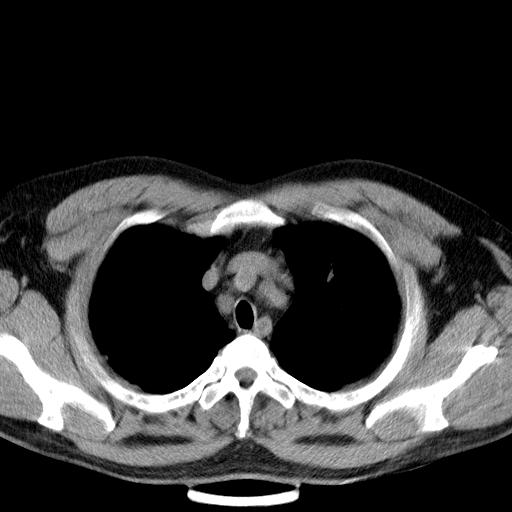

患者男性 35 主因发热咳嗽四天,血象不高,心肺听诊未见异常,无其它病史及传染病接触史。

两肺散在大小不等小结节影,下野较多,纵隔淋巴结增大。考虑:1、慢性血播性肺结核;2、霉菌病?3转移瘤待排。

两肺多发结节,部分病灶边缘不清,且示毛玻璃影。分布特点为沿血管支气管分布。

结合临床考虑;1,炎性肉芽肿性病变;霉菌?过敏性肺炎?2,韦格氏肉芽肿。3,转移瘤。

双肺散在多发类圆形结节灶,边缘较光滑,纵隔淋巴结肿大,考虑转移瘤

肺内多发大小不等结节影,以外周为著,纵隔见多个淋巴结肿大;结果病人,35岁,有发烧咳嗽等病史,首先考虑血源性肺脓肿可能性大,建议积极抗炎治疗后复查,除外转移瘤或韦格氏肉芽肿.